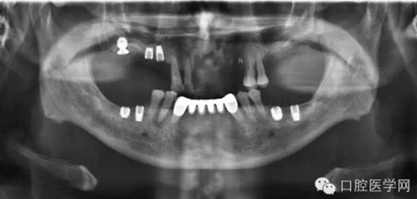

那么今天我給大家展示臨床上比較常見的幾種品牌的種植體的X光片,網(wǎng)友們可以通過(guò)X光片來(lái)仔細(xì)查看不同種植體之間的區(qū)別。因?yàn)楸救四芰τ邢?,不能每一樣種植體都拿來(lái)嘗試使用,所以我目前收集到的種植體的X光片數(shù)量有限,但是本人日后還會(huì)不斷的去尋找不同品牌種植的資料,然后補(bǔ)充道這篇文章中,以供大家參考。

需要特殊聲明的是:以下所有的照片中有本人自己的病例術(shù)后X光片,也有本人在網(wǎng)絡(luò)上搜集到的X光片(并非本人的臨床病例),所以在此暫不討論種植體手術(shù)植入的角度和設(shè)計(jì)方案等問題,本文的主要目的是像廣大讀者展示不同品牌種植體在植入頜骨內(nèi)拍攝X光片后所顯示的形狀,用以區(qū)別不同品牌的種植體。

首先介紹一下最有特點(diǎn)的種植體,美國(guó)BICON種植體(美國(guó)百康種植體)

上面這張圖片是百康種植體的照片,屬于短種植體一類,獨(dú)特的魚嵴式設(shè)計(jì)是它最大的特點(diǎn)。

下面這張圖片是百康種植體的X光片。